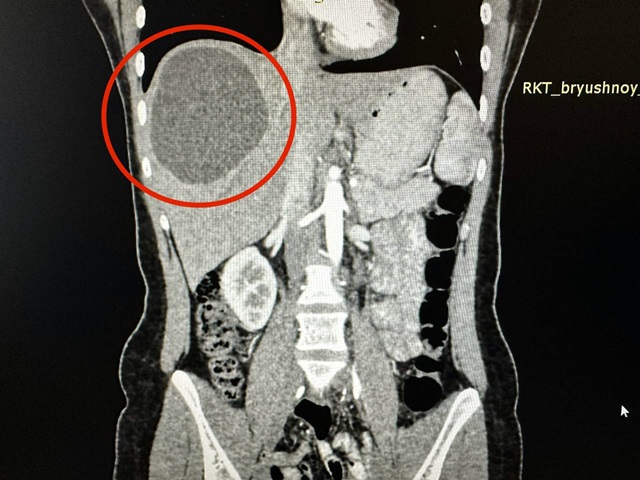

В Казани хирурги отделения хирургии №2 Республиканской клинической больницы (РКБ) удалили 19-летней пациентке огромный эхинококк, сообщила пресс-служба медучреждения.

Врачи пояснили, что несколько месяцев назад девушка обратилась к докторам с сильными болями. Во время обследований врачи обнаружили паразитов в печени, которые образовались в кисту размером 20 на 15 сантиметров.

Сначала медики назначили девушке химиотерапию, чтобы убить паразитов. Через три месяца ее пригласили на операцию. Из-за того, что паразиты поразили здоровые ткани печени, хирургам пришлось убрать практически треть органа.